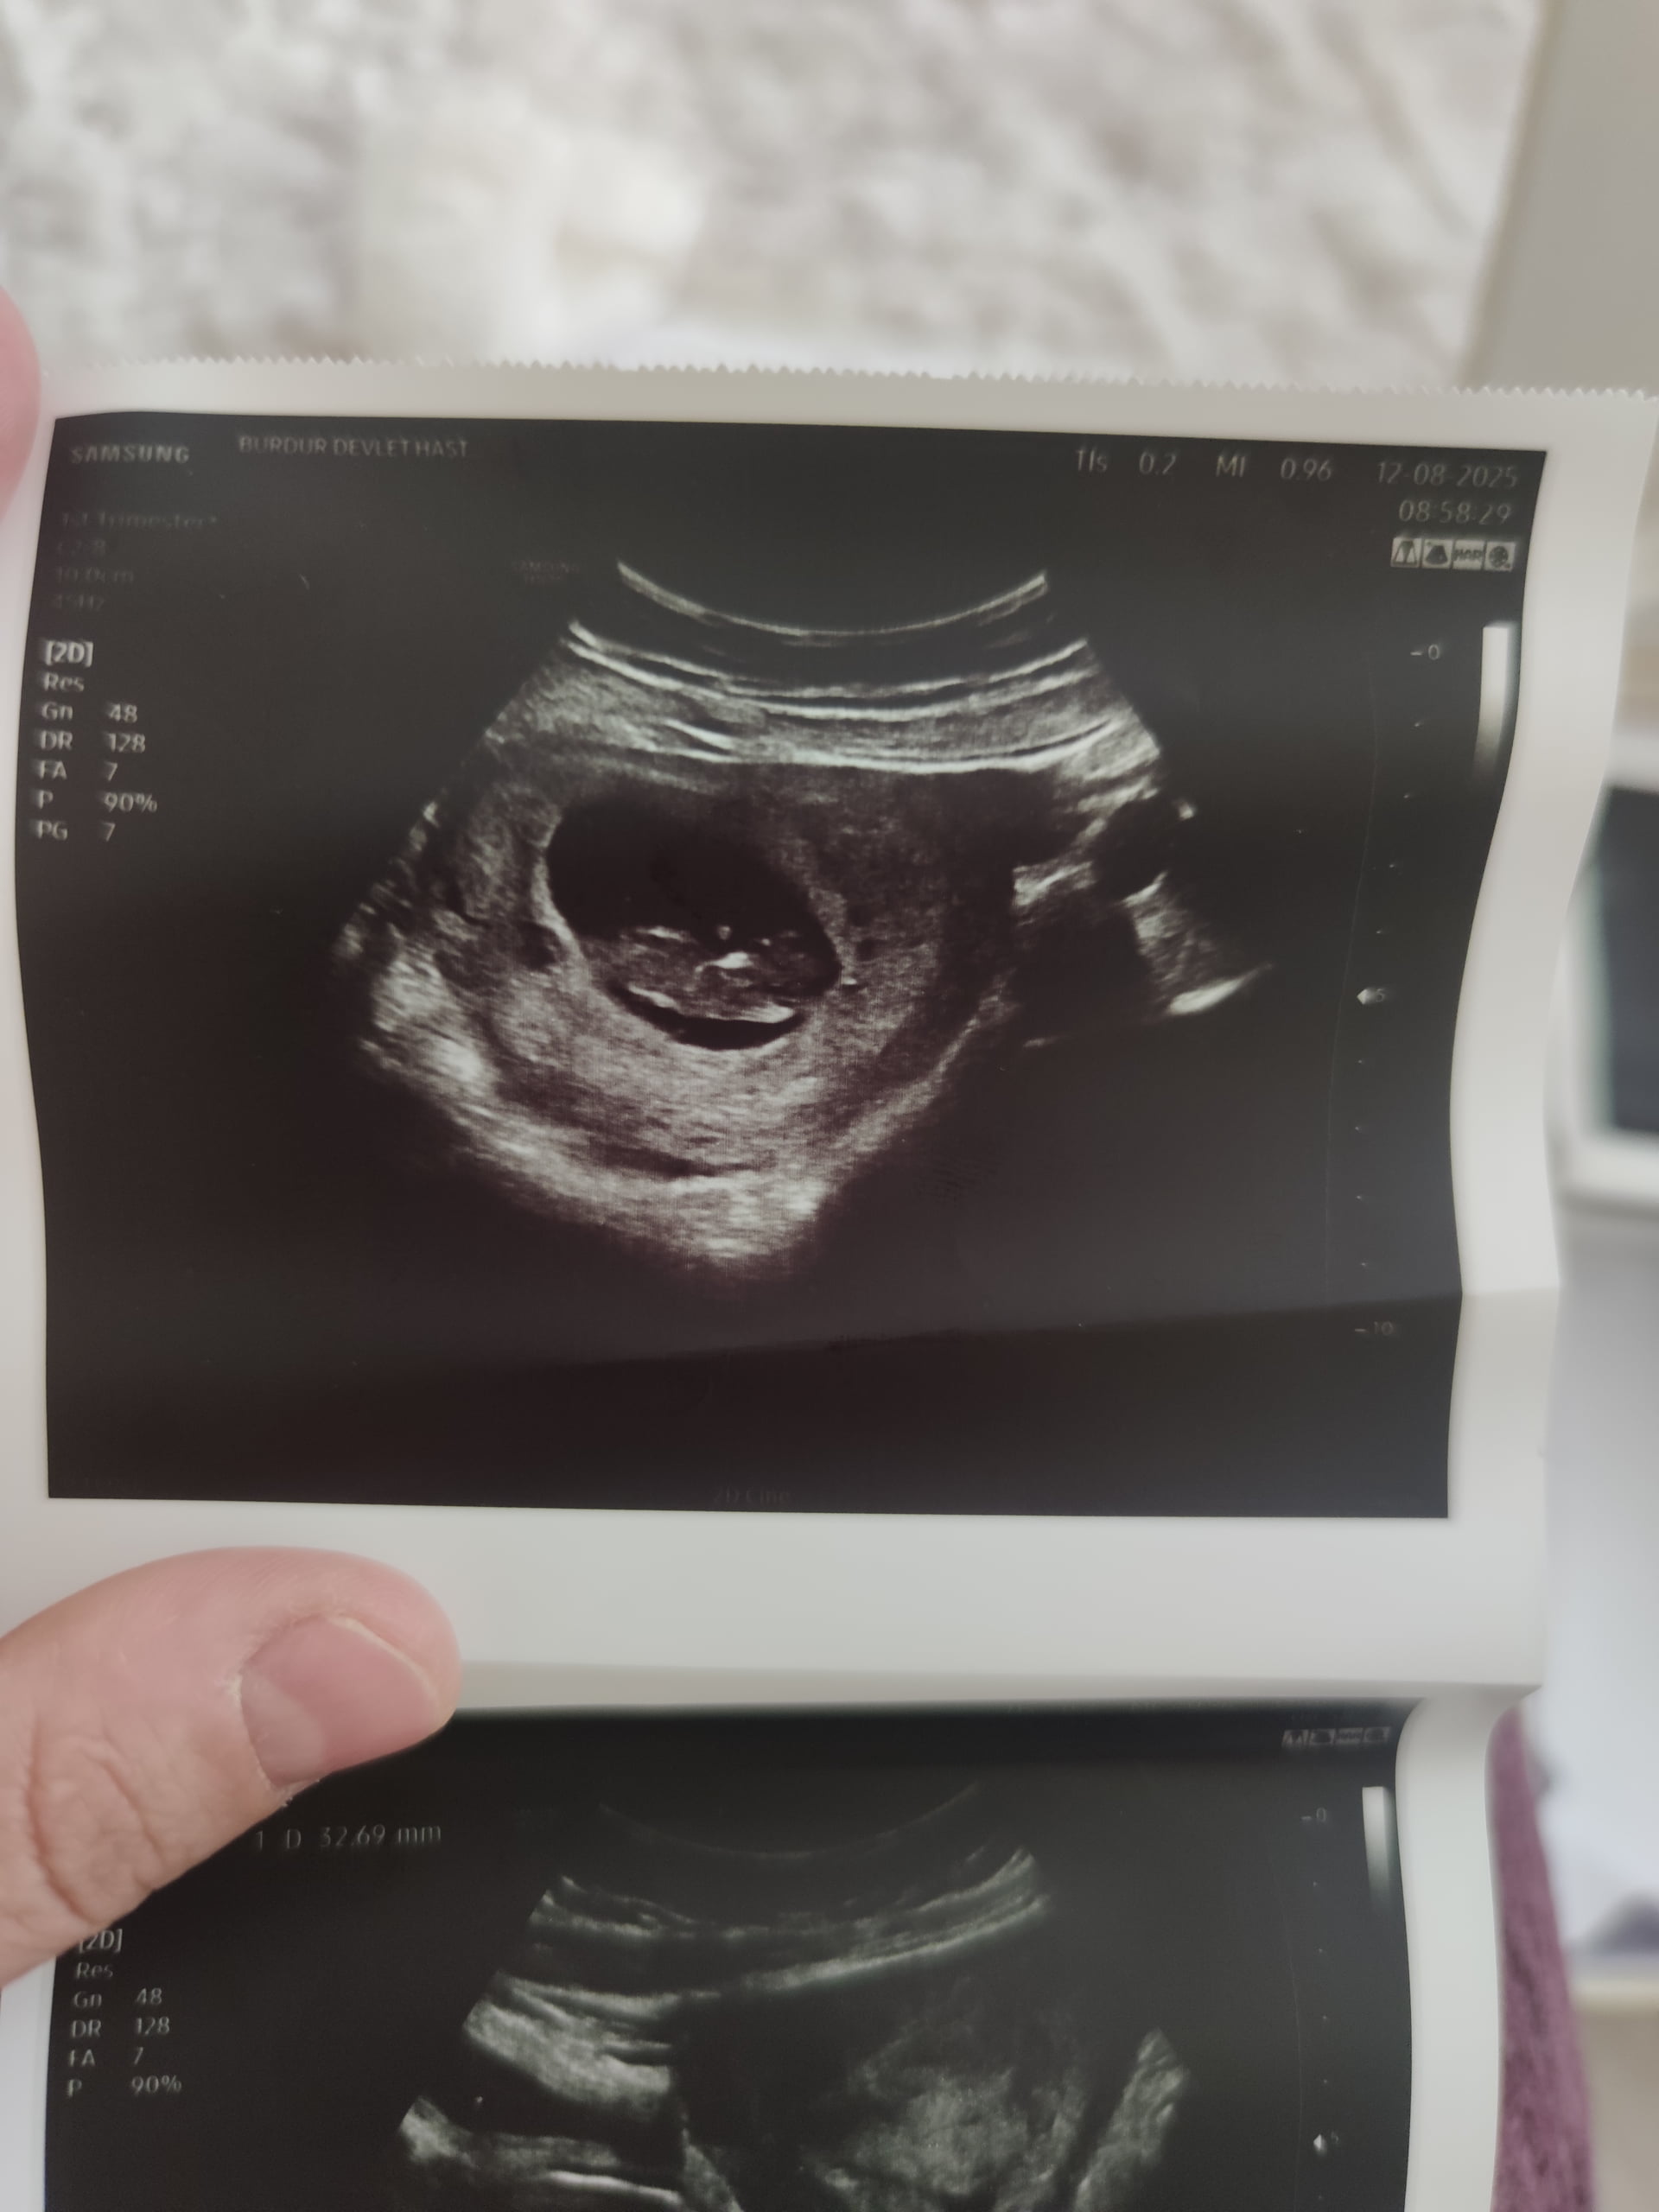

Cinsiyet tahmini yapalım

Erkek bebiş kesesi gibi ![]()

@Neriman Kız bebek kesesi canım biraz daha büyüyünce tekrar atarsın bakarız ama prenses gibi geldi bana

Kız bebeğe benziyor

Burda kese yuvarlak benim kesemede benzettim erkek gibi duruyor büyümüş bebiş biz tahmin ediyoruz takdir Allah’ın daha belli olmadı mı önce ki kese şekline göre kız demiştim ama büyüyünce benim kesem gibi yuvarlak olmuş ve aşağıda tutunmuş hakkında hayırlısı olsun canım @Neriman Net öğrendiğim zaman etiketlersin beni